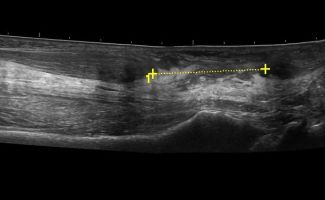

Foot Tendons

Foot Ultrasound allows the diagnosis of tendonitis, tenosynovitis, and rupture in the following tendons:

- Achilles Tendon

- Peroneal Tendons

- Flexor Tendons

- Extensor Tendons